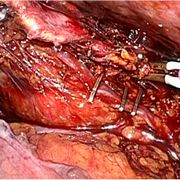

手術画像